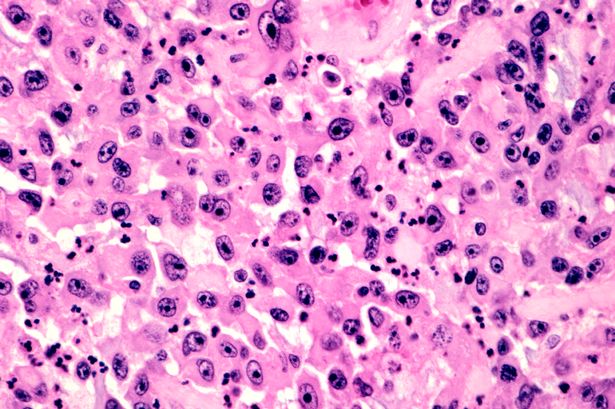

Robotët mikroskopikë mund të përdoren së shpejti si armë në betejën e njeriut për të luftuar kancerin. Disa shkencëtarë zviceranë kanë projektuar një makineri të jashtëzakonshme, e cila mund të programohet për të shkatërruar tumoret pa prekur qelizat e shëndosha.

“Por nëse kemi më shumë kontroll mbi këto agjentë dhe arrijmë të shënjestrojmë objektivin e duhur, mund të arrijmë të minimizojmë këto efekte anësore,” tha ai. Robotët në fjalë kanë një formë sferike, si dhe janë kaq të vegjël saqë 1,200 prej tyre mund të përfshihen në një hapësirë që zë një pikselë.